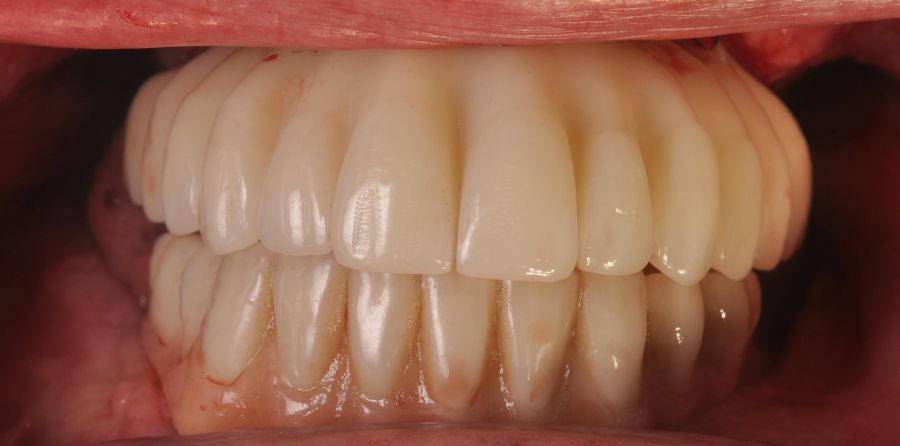

Two months later, with the soft tissues healed around the connections (Figure 16), a new intraoral scanning was made of the implants and the provisional prosthesis for future restoration. A FRI type passivity test (rigid impression splint) was manufactured with an aluminium structure to assess the correct fit on the implants (Figure 17). For implant-supported rehabilitation, a sintered structure was made in chrome-cobalt with machined bases covered with acrylic resin teeth from Bredent® (Figures 18-21).